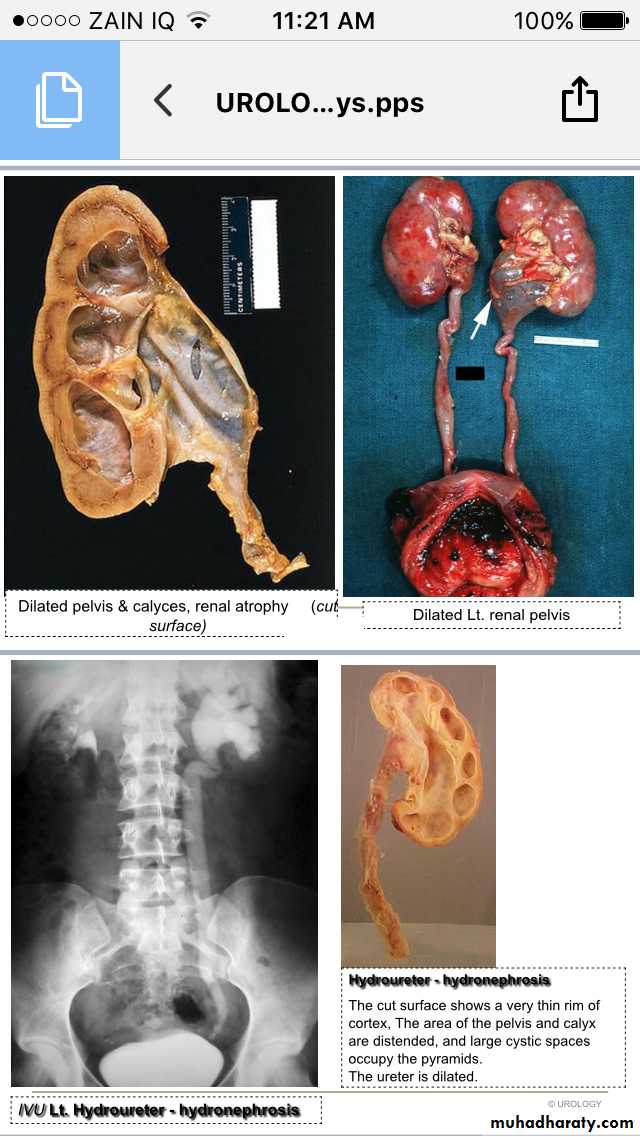

Hydronephrosis-Hydroureter